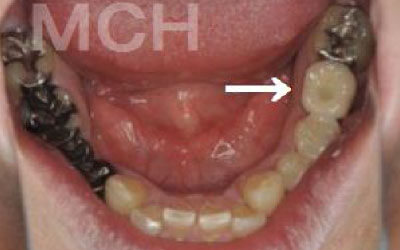

歯が抜けたままにしていたら、隣の歯が動いてしまいました。どうすればよいでしょうか?

軽度の歯のズレであれば調整や詰め物で対応可能ですが、大きく傾いてしまった場合は矯正治療や被せ物が必要になることがあります。

ズレがひどくなる前に、できるだけ早めの検査と治療を受けることをおすすめします。

少しの位置ズレであれば、噛み合わせの調整や小さな詰め物で改善することが可能です。

ただし、抜けてから数年が経過して大きく歯が傾いてしまった場合は、歯並びの矯正を行うか、歯を大きく削って被せ物をする必要があります。

2 歯が傾いてくる、落ちてくる

歯は互いに支え合ってバランスを保っています。つまり、歯が抜けるとその支えがなくなり、抜けた部分の隣の歯が倒れたり、上の歯が下に沈んだりすることがあります。